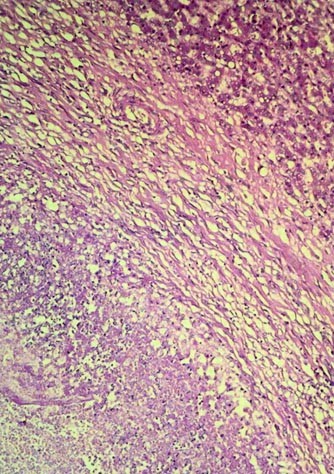

The image of the liver lesion shows a wide fibrotic reaction surrounding necrotic areas (at the bottom). (Hematoxylin–eosin staining, original magnification, 200×.)